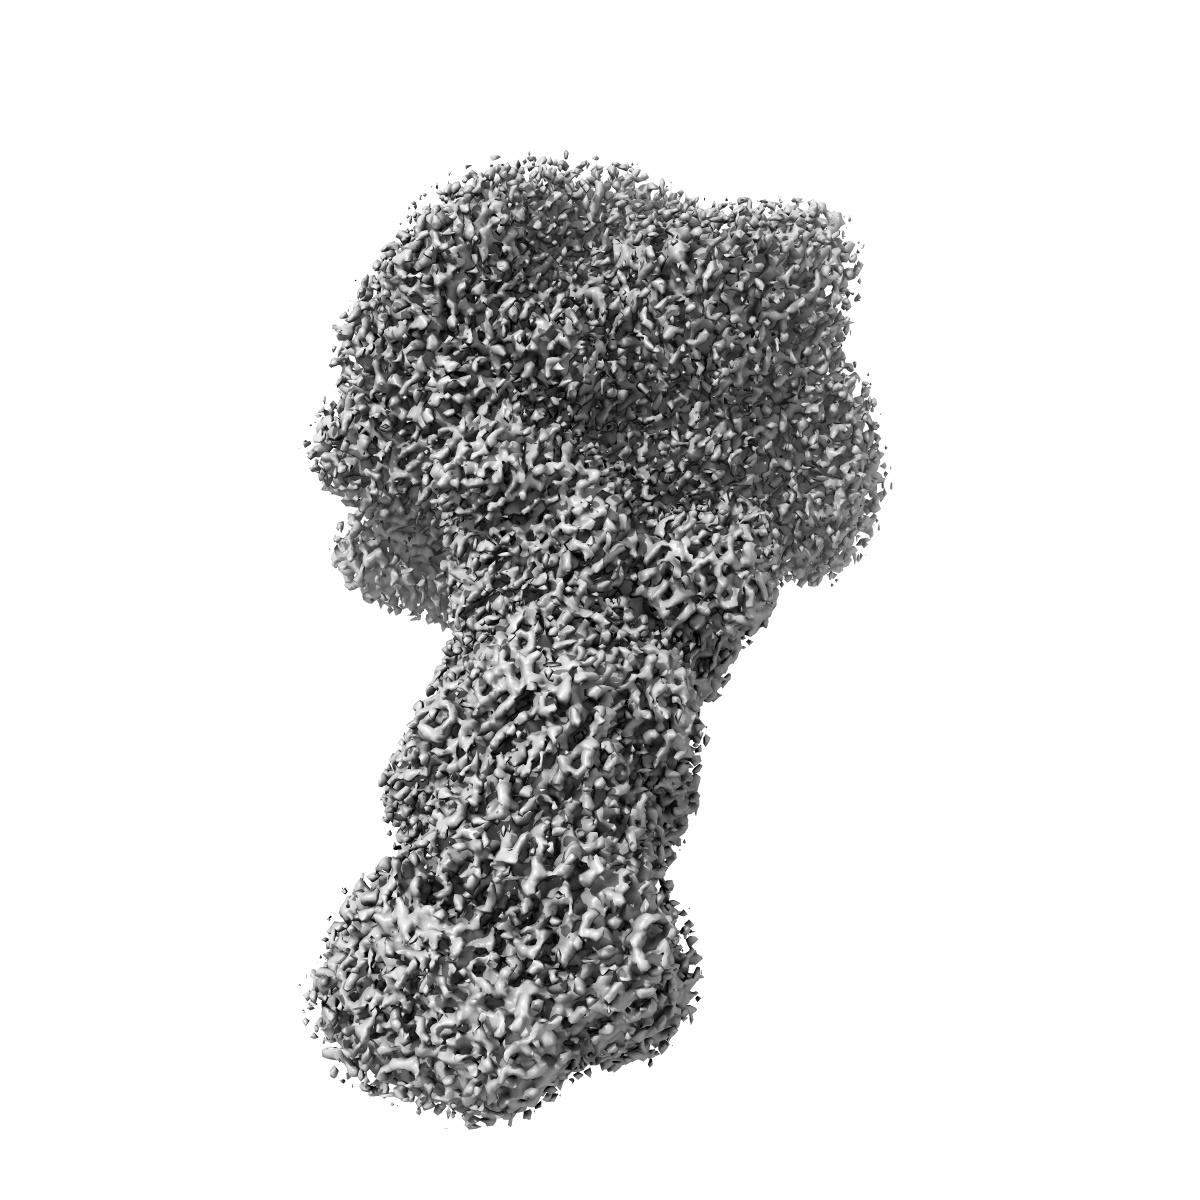

EMD-20906

CryoEM Structure of the active Adrenomedullin 2 receptor G protein complex with adrenomedullin 2 peptide

Single-particle2.3 Å

Sample: AM2:CLR:RAMP3:GasDN:Gb1:Gg2:Nb35 GPCR Complex

Structure and Dynamics of Adrenomedullin Receptors AM1and AM2Reveal Key Mechanisms in the Control of Receptor Phenotype by Receptor Activity-Modifying Proteins.

(2020) Acs Pharmacol Transl Sci , 3 , 263 - 284